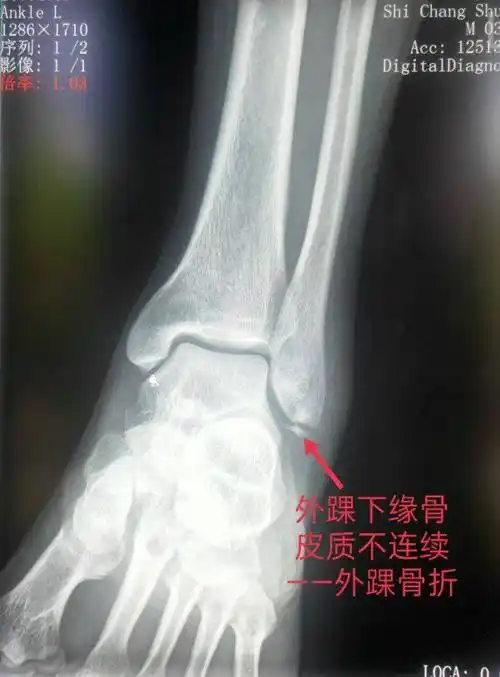

骨关节有哪些脚踝属于什么关节